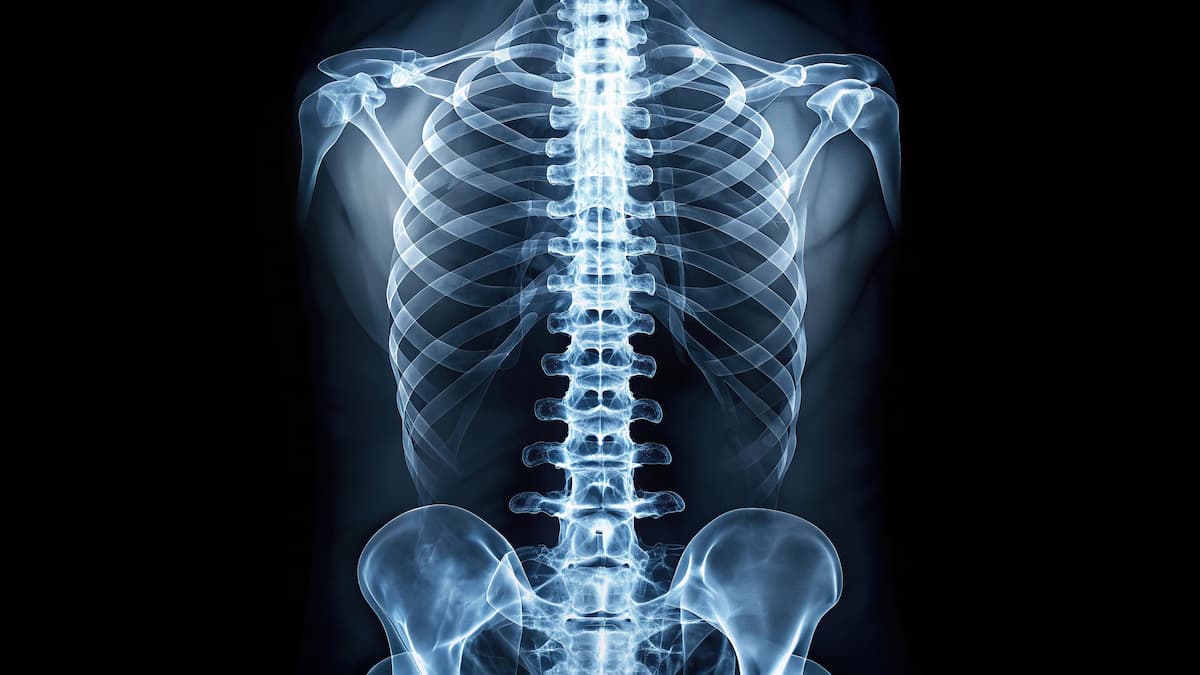

Vertebral fractures are common in glucocorticoid-associated osteoporosis and are a clinical indicator of osteoporosis in young patients. | Image credit: Hugnaka - stock.adobe.com

“Vertebral fractures are now recognized as a hallmark of glucocorticoid-associated osteoporosis and serve as a clinical indicator of osteoporosis in young individuals regardless of DXA bone density,” the authors wrote. “Recent International Care Considerations for bone health monitoring in DMD advocate for regular lateral spine imaging to detect vertebral fractures, emphasizing that relying solely on symptoms may underestimate their frequency in this high-risk population.”